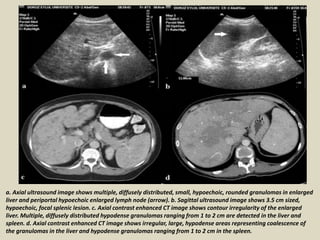

a. Axial ultrasound image shows multiple, diffusely distributed, small, hypoechoic, rounded granulomas in enlarged

liver and periportal hypoechoic enlarged lymph node (arrow). b. Sagittal ultrasound image shows 3.5 cm sized,

hypoechoic, focal splenic lesion. c. Axial contrast enhanced CT image shows contour irregularity of the enlarged

liver. Multiple, diffusely distributed hypodense granulomas ranging from 1 to 2 cm are detected in the liver and

spleen. d. Axial contrast enhanced CT image shows irregular, large, hypodense areas representing coalescence of

the granulomas in the liver and hypodense granulomas ranging from 1 to 2 cm in the spleen.